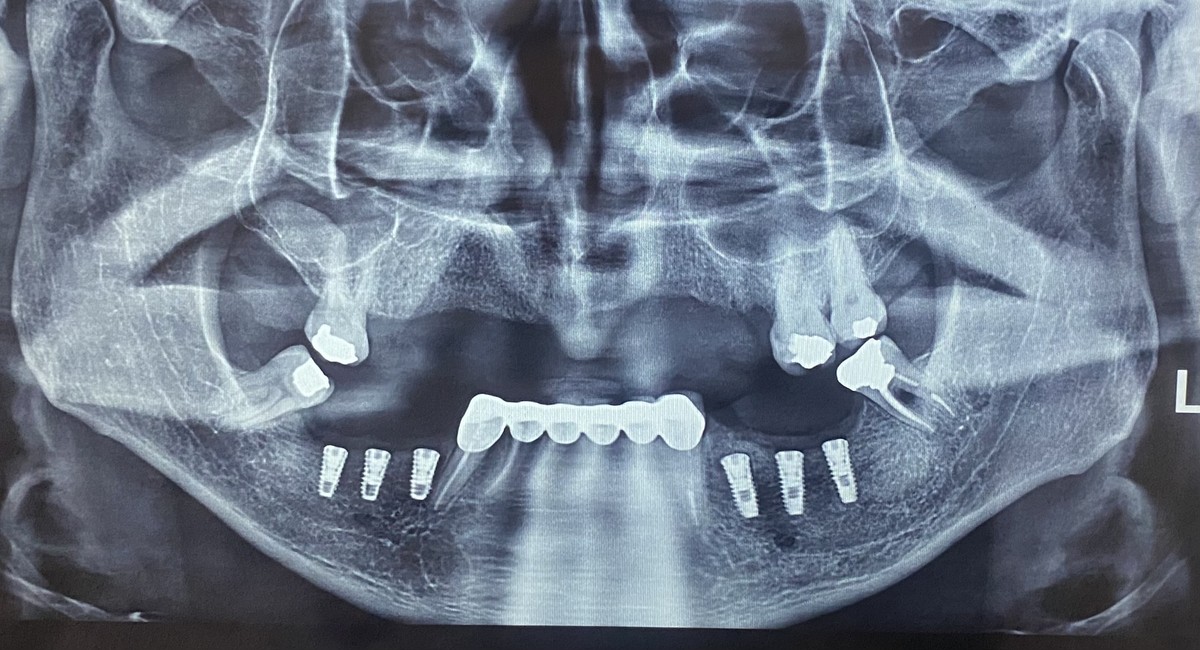

لمینیت سرامیکی دندان(طراحی لبخند) کامپوزیت ونیر دندان (طراحی لبخند) ایمپلنت و کلیه جراحی های تخصصی فک و صورت توسط جراح و متخصص دهان و فک و صورت کلیه خدمات دندانپزشکی به صورت تخصصی با بالاترین کیفیت توسط بهترین دندانپزشکان و در محیط کاملا vip

کلینیک دندانپزشکی دندانپزشکی زیبایی مرکز کامپوزیت دندان مرکز لمینت دندان مرکز ارتودنسی دندان دندانپزشکی کودکان دکتر ارتودنسی کودکان دندانپزشکی اطفال دکتر دندانپزشک متخصص ایمپلنت دندانپزشکی شبانه روزی عصب کشی جراح دندانپزشک جراح دندان عقل جراح لثه جراحی لثه با لیزر متخصص درمان ریشه دندان متخصص لمینت دندان متخصص ارتودنسی ایمپلنت فوری اصلاح طرح لبخند بلیچینگ دندان دندانپزشکی بدون درد کاشت دندان متخصص پروتز دندان ایمپلنت دیجیتال لیفت لثه با لیزر دندانپزشکی با لیزر دکتر دندانساز ایمپلنت اقساطی مشاهده بیشتر